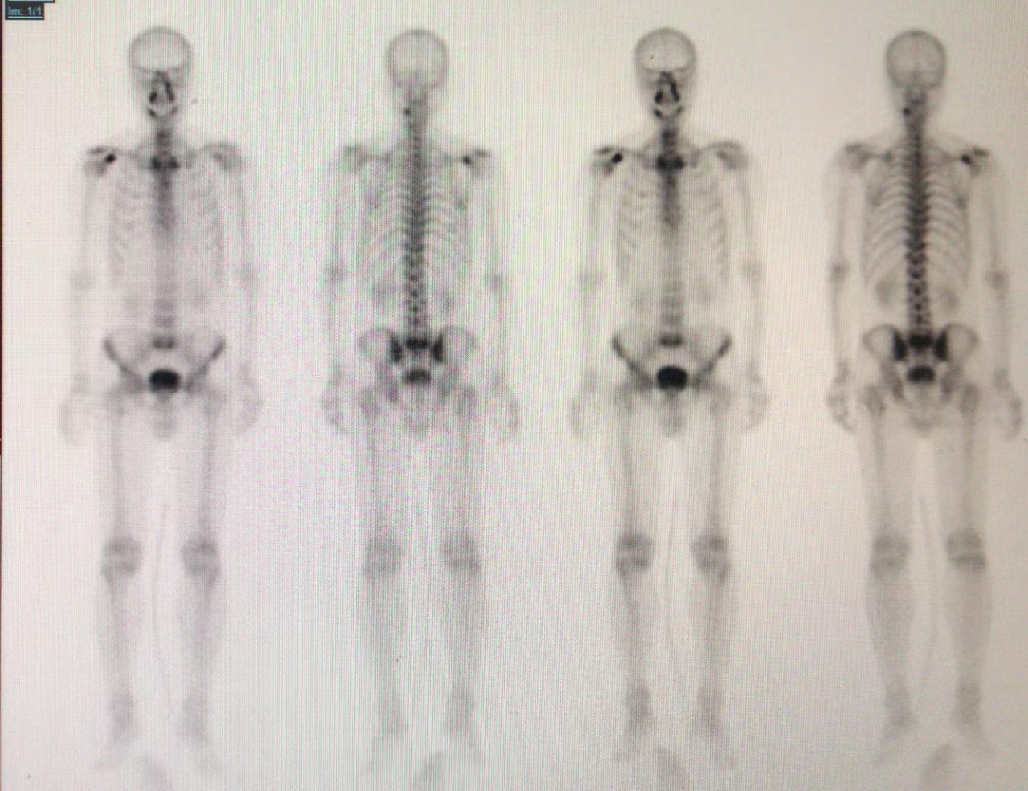

全身骨显像:上段颈椎左侧、L5-S1、右肩代谢异常活跃,考虑良性病变可能。建议定期复查全身骨显像。